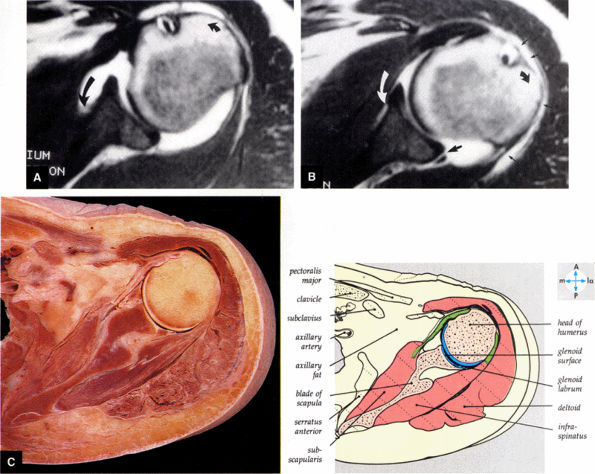

FIGURE 8.86 ● Normal variation in morphology of the subscapularis bursa is seen with (A) internal rotation and (B) external rotation on gadolinium-enhanced T1-weighted axial images. The subscapularis bursa has the appearance of a type 3 capsular insertion (long black curved arrow) in internal rotation (short black curved arrow) and a type 1 capsular insertion (long curved white arrow) in external rotation (short black curved arrow). Gadolinium contrast between the posterior band of the IGHL and the posterior labrum (large straight black arrow) and gadolinium contrast lateral to the humeral head in the subacromial bursa (small straight black arrows) are indicated. (C) A transverse section at the level of the humeral head shows the relations of the glenohumeral joint.